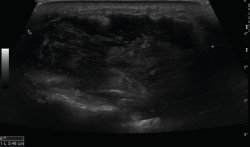

El ultrasonido se puede usar en el diagnóstico de numerosas patologías y puede guiar en procedimientos diagnósticos y terapéuticos(5).

Su indicación fundamental es en el diagnóstico de las lesiones de partes blandas superficiales.

Las estructuras específicas más adecuadas para este estudio incluyen tendones, músculos y ligamentos, además de masas periarticulares de tejidos blandos. Es útil para el diagnóstico de derrame articular, engrosamiento sinovial, bursitis, cuerpos libres intraarticulares, gangliones, quistes, roturas ligamentosas y tendinosas, tendinitis y fracturas ocultas(6).

En el estudio musculoesquelético se utiliza una sonda lineal con alta frecuencia, de entre 9 y 13 mHz.